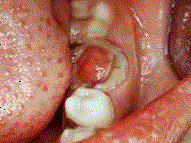

问题 慢性增生性牙髓炎的特点是息肉 ( )

选项 A.充满整个龋洞 B.与牙髓相连 C.与牙龈相连 D.与牙周膜相连 E.与牙槽骨相连

答案 B